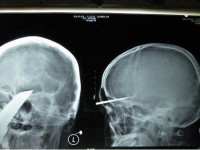

Kineski tinejdžer preživio zabijanje mača u lubanju